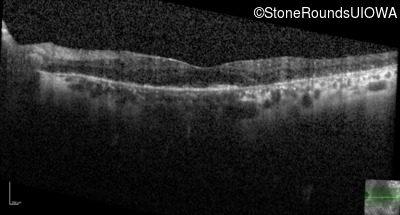

Optical Coherence Tomography - Right - 20/30

Exemplar / OCT Stack